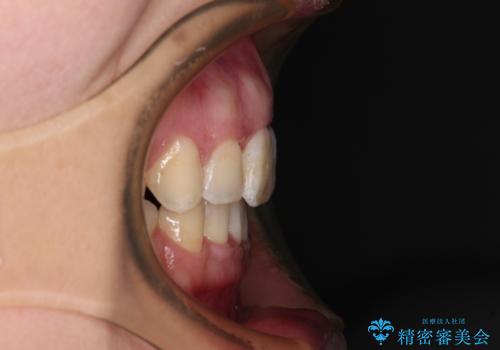

- 出っ歯と口の閉じにくさ、デコボコを気にして来院された患者様です。

口元の突出感を改善するため、上下左右第一小臼歯4本の抜歯を行い、ワイヤー装置による矯正治療を行うこととしました。

上下前歯の距離が大きかったため、上下の歯が接触するまでに時間がかかりました。

それでも目安である2年半で終えることができ、患者様には大変満足していただけました。